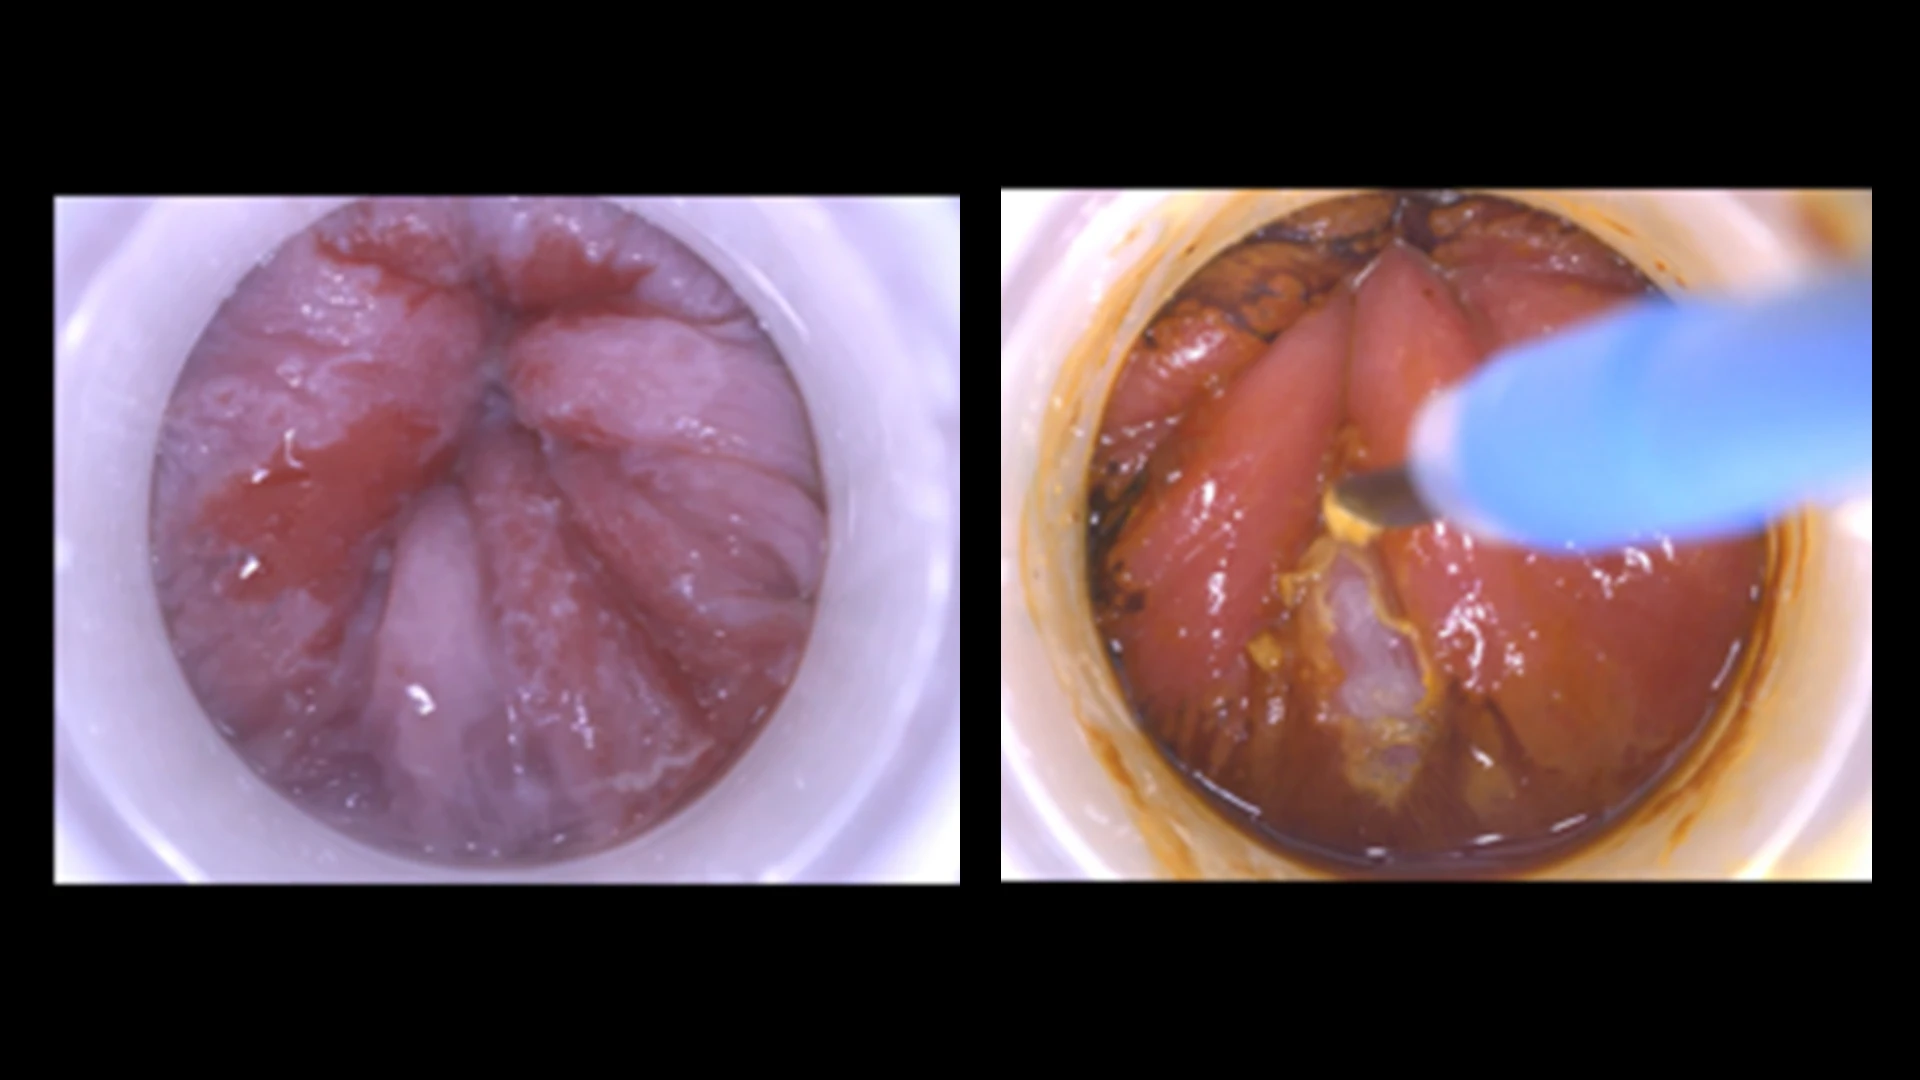

Dr. Kim partnered with medical device manufacturers to improve a high-resolution anoscopy device that would more effectively identify anal lesions. The new device can view cells at 38x and 59x magnification, compared to 3x or 4x magnification with a surgical scope. “It’s almost as powerful as a microscope,” he says.

High-resolution anoscopy can effectively identify suspicious lesions and lead to less-invasive procedures. Traditionally, suspicious lesions identified in an anal Pap test are biopsied and treated in the operating room across a series of visits. After gaining experience in high-resolution anoscopy, Dr. Kim developed a technique that most patients can tolerate without anesthesia. He now performs the screening and treatment during in-office visits for 86 percent of his patients.

Early anal lesions (precancerous without deep invasion) are identified and treated by burning them off in the office.